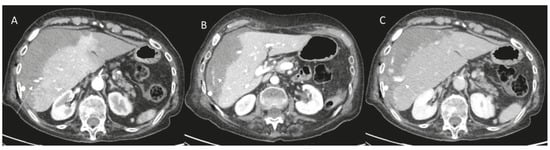

- Choi, D.; Lim, H.K.; Kim, M.J.; Kim, S.J.; Kim, S.H.; Lee, W.J.; Lim, J.H.; Paik, S.W.; Yoo, B.C.; Choi, M.S.; et al. Liver abscess after percutaneous radiofrequency ablation for hepatocellular carcinomas: Frequency and risk factors. AJR Am. J. Roentgenol. 2005, 184, 1860–1867. [Google Scholar] [CrossRef]

- Malekzadeh, S.; Widmer, L.; Salahshour, F.; Egger, B.; Ronot, M.; Thoeny, H.C. Typical imaging finding of hepatic infections: A pictorial essay. Abdom. Radiol. 2021, 46, 544–561. [Google Scholar] [CrossRef]

- Catalano, O.; Sandomenico, F.; Raso, M.M.; Siani, A. Low mechanical index contrast-enhanced sonographic findings of pyogenic hepatic abscesses. AJR Am. J. Roentgenol. 2004, 182, 447–450. [Google Scholar] [CrossRef]

- Giambelluca, D.; Panzuto, F.; Giambelluca, E.; Midiri, M. The “double target sign” in liver abscess. Abdom. Radiol. 2018, 43, 2885–2886. [Google Scholar] [CrossRef] [PubMed]